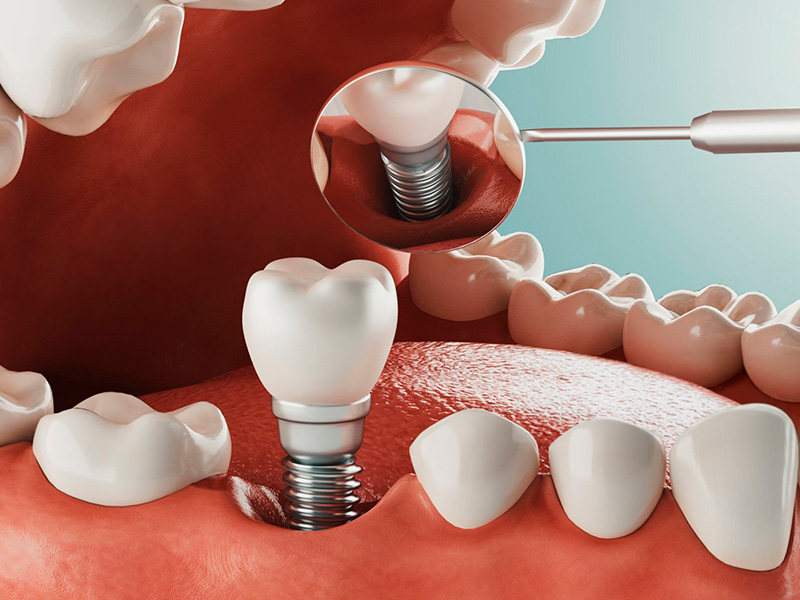

Sustitución definitiva de piezas perdidas mediante implantología digital avanzada. Soluciones fijas, naturales y sin dolor diseñadas a tu medida.

Diagnóstico Digital Sin Errores

En nuestra clínica no adivinamos. Utilizamos tecnología de vanguardia para planificar tu cirugía antes de comenzar.

- Tomografía Computarizada 3D para máxima precisión ósea.

- Escaneo intraoral (adiós a los moldes molestos).

- Planificación virtual de implantes para cirugías más rápidas.

Fase quirúrgica ágil en 2 citas, consolidando la restauración estética definitiva tras su proceso de osteointegración.

Restauración Unitaria